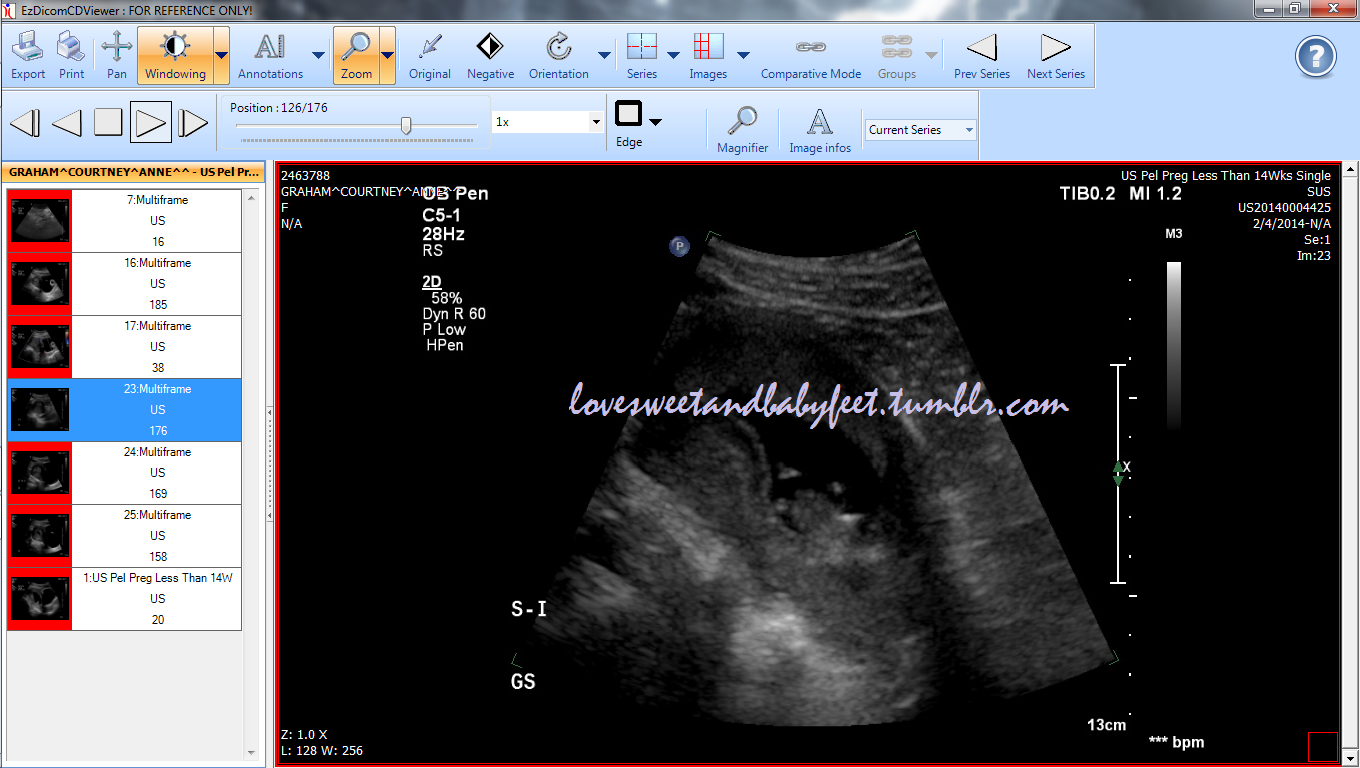

I'm okay with patiently waiting for the 20 week mark, I'm just curious as to whether or not this method is true for me. I asked at my last ultrasound, but they didn't tell me what side the placenta was on...so basically, are any of you good at reading ultrasounds and deciphering locations of different things in the picture?

My 6 week and 10 week ultrasounds are attached. (The 6 week is transvaginal)